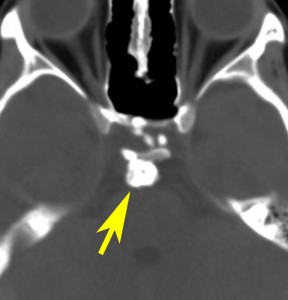

7歳の子が視力障害で発症しました。両耳側半盲という症状です。典型的な鞍隔膜下頭蓋咽頭腫です。ガドリニウム造影剤を入れないMRIでみえる,黄色い矢印の先の白い高信号は抗利尿ホルモンです。ですから下垂体機能もまだ残っていて,尿崩症はありません。視力障害が戻らないことがあるのでなるべく早く,経鼻的な手術で摘出した方がいいものです,簡単 o(^-^)o